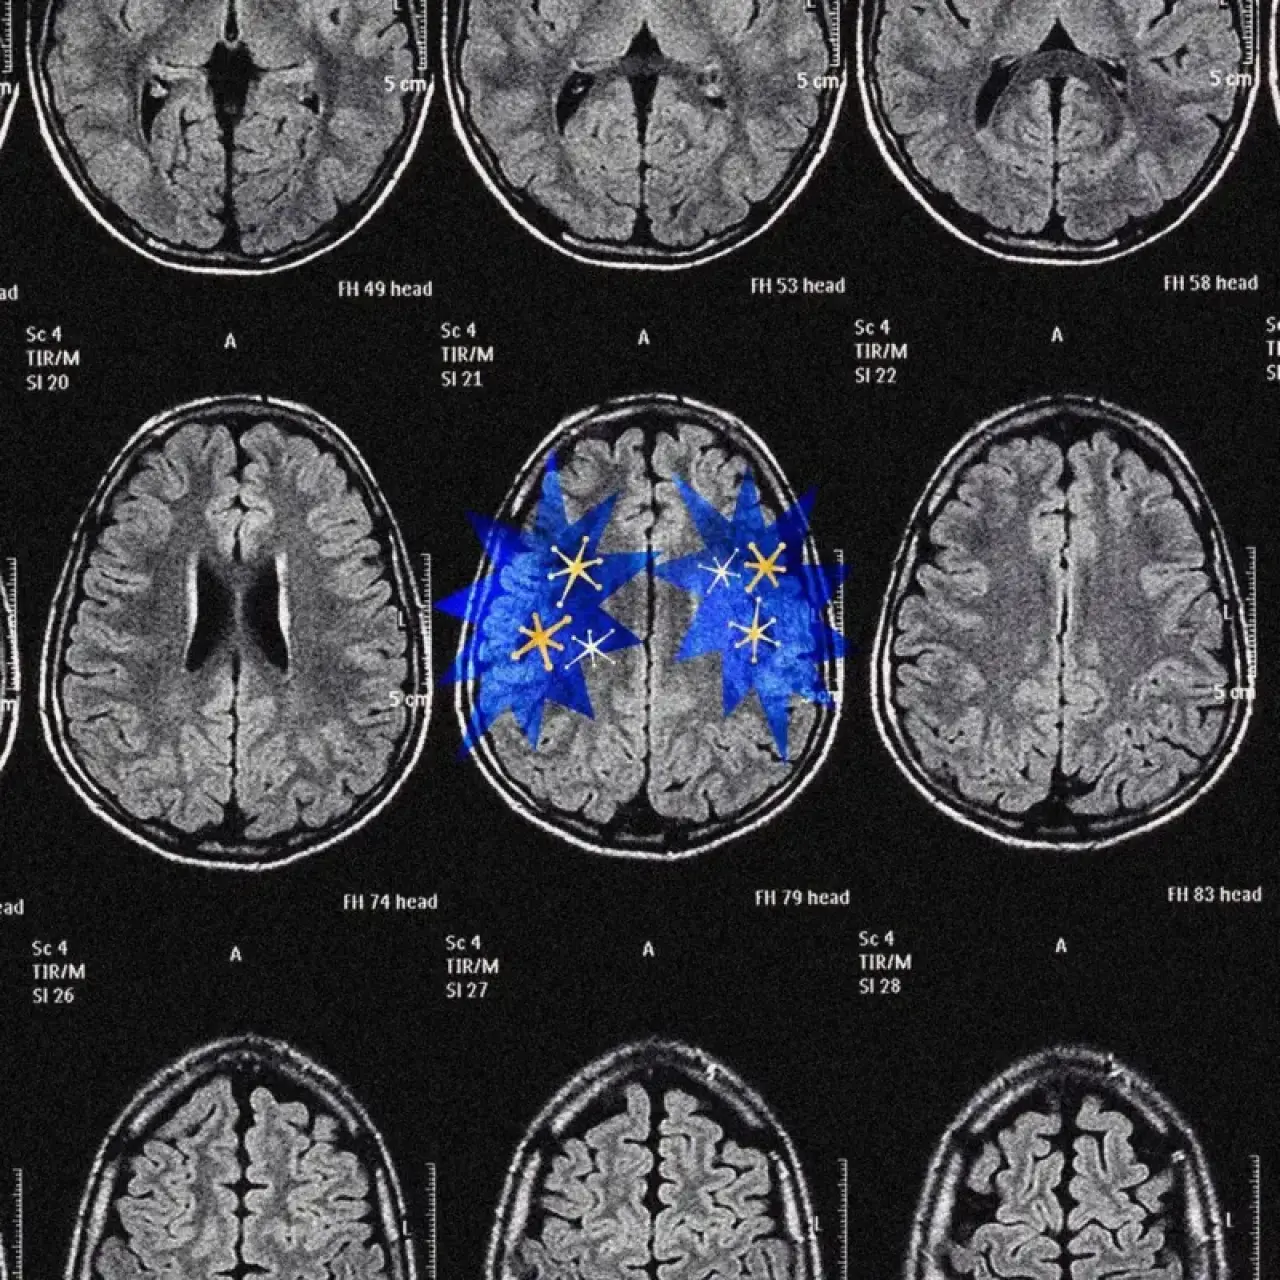

Dopamin yoksa: beyin duruyor

Bu sistemin çarpıcı örneklerinden biri, 20. yüzyılın başında görülen ve “uyku hastalığı” olarak bilinen salgında gözlemlendi. Beyindeki dopamin üreten merkezlerin zarar gördüğü hastalar, hayati refleksler dışında neredeyse hiçbir şey yapmak istemiyordu. Yemeği çiğniyorlar ancak uzanıp almıyorlardı.

Uzmanlar, dopaminin yokluğunda beynin adeta “karanlık bir oda”ya çekildiğini ve motivasyonun çöktüğünü belirtiyor.